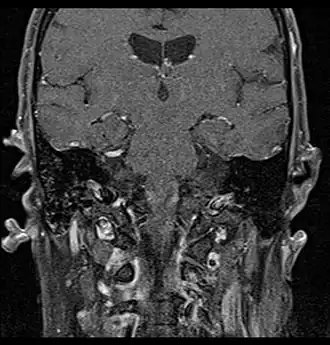

Primary treatment for this cancer, regardless of body site, is surgical removal with clean margins. This surgery can prove challenging in the head and neck region due to this tumor's tendency to show a perineural discontinuous growth, meaning that it follows nerves and different "nests" of the tumor can exist without a connection to the original tumor. Therefore, MRI-images should be analysed following nerve tracts up to the brainstem. Adjuvant or palliative radiotherapy is commonly given following surgery. For advanced major and minor salivary gland tumors that are inoperable, recurrent, or exhibit gross residual disease after surgery, fast neutron therapy is widely regarded as the most effective form of treatment.[13][14][15][16] Chemotherapy is used for metastatic disease. Chemotherapy is considered on a case-by-case basis, as data on the positive effects of chemotherapy are limited. Clinical studies are ongoing, however.

Coronal MRI showing right parotid adenoid cystic carcinoma with perineural spread of tumor: The tumor originates in the right parotid gland and spreads along the trigeminal nerve via the auricuotemporal branch extending intracranially through the foramen ovale at the skull base towards Meckel's cave. -

Coronal MRI showing right parotid adenoid cystic carcinoma with perineural spread of tumor along the facial nerve extending to the stylomastoid foramen -